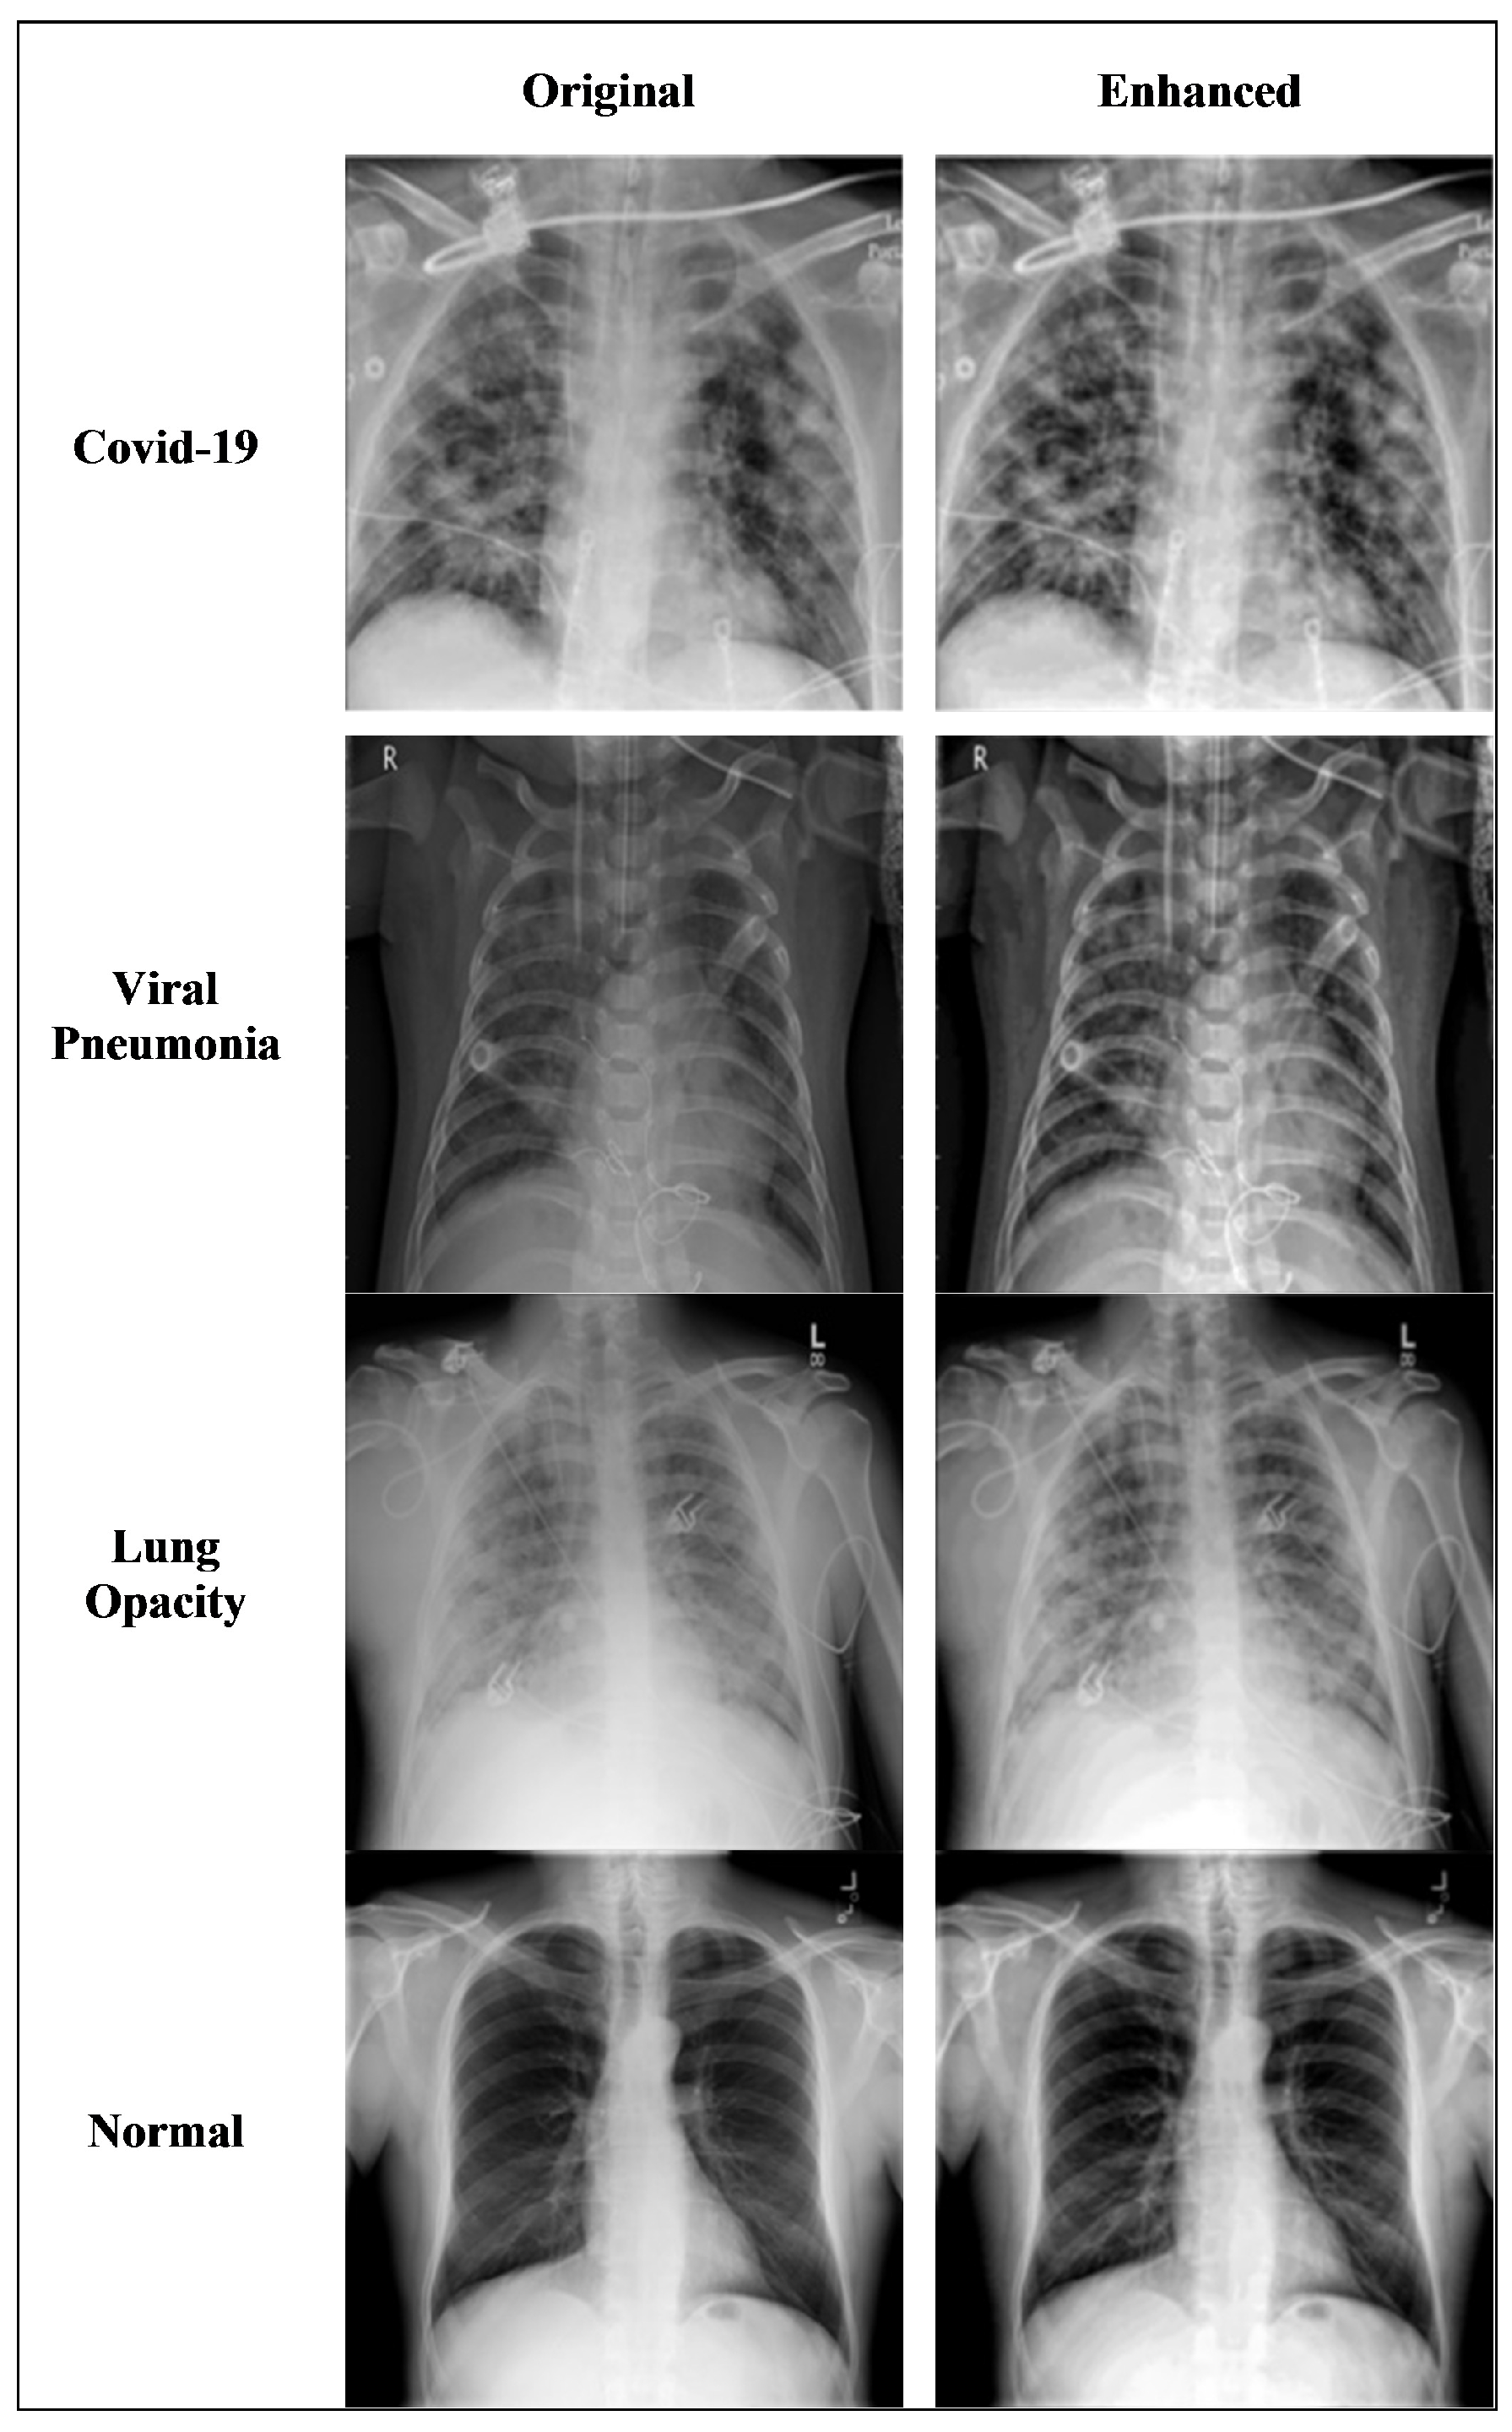

Image enhancement is required both for ensuring the original image data is clear and also for generating additional images with which to apply data augmentation techniques. The technique requires manipulating the edge-aware local contrast that results in the enhancement and flattening of the contrast of the image through smoothing and increasing the image details. This technique, however, keeps the strong edges as they are by choosing a threshold value that defines the minimum intensity amplitude of the strong edges to be left unchanged, while simultaneously providing the required smoothing and enhancement. We chose 0.2 as the threshold value and 0.5 as the enhancement value during the image enhancement process. Smoothing the contrast of the modified images is done using anisotropic diffusion filter. Fourier transform is applied to shift the zero-frequency component to the center of the spectrum.

Figure 4 shows the results of applying the enhancement technique to the original images of four different types: COVID-19, viral pneumonia, lung opacity, and normal patients. The visual comparison between the original images and the enhanced images clearly shows that the images are smoothed and enhanced while keeping the strong edges intact.